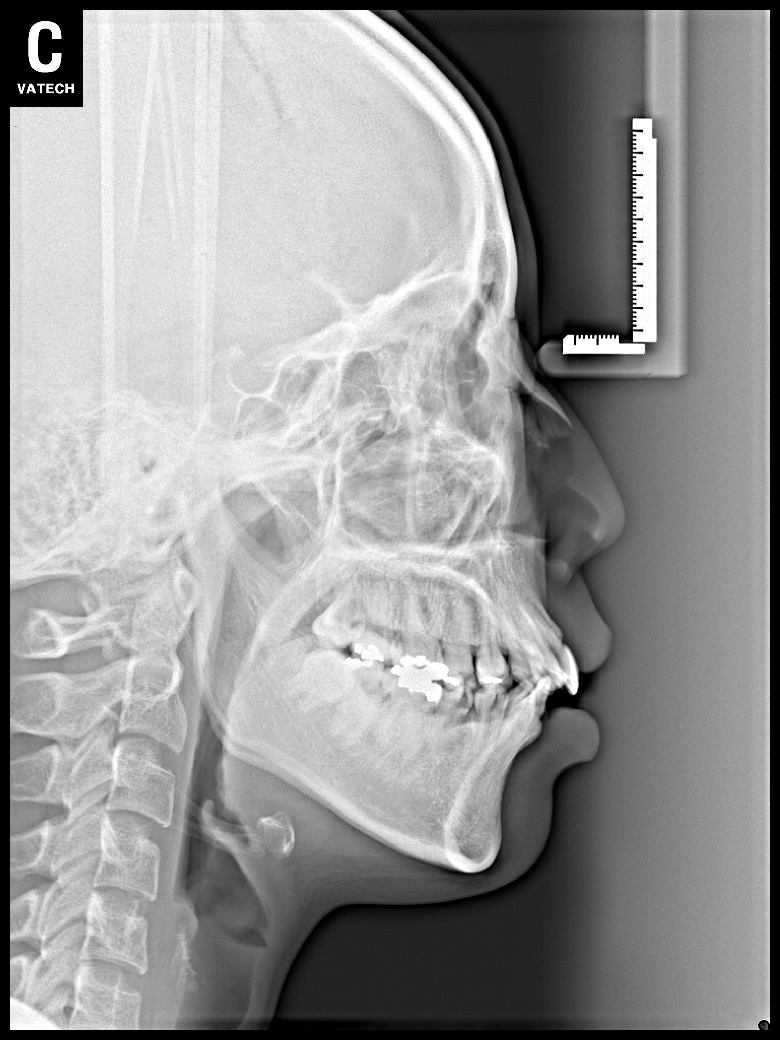

치료 전 사진입니다.